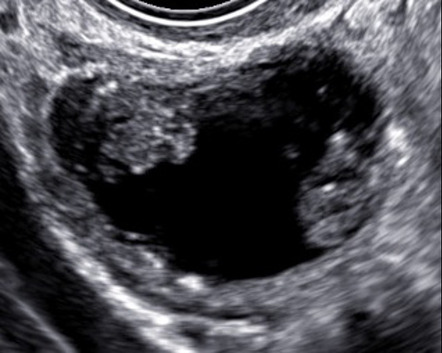

- Pelvic ultrasound (TAS or TVS)

- Multiple septations

- Cystic and solid components (papillary etc.)

- Larger than cysts (> 7cm)

- Neovascularization